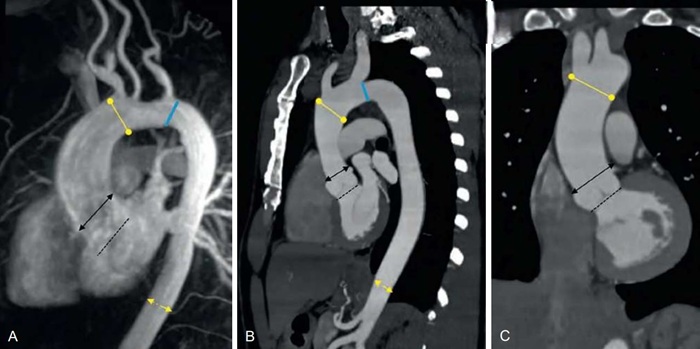

Компьютерная томография дает снимки, по которым можно оценить состояние стенок сосудов, их форму, дефекты развития и пороки. Возможность построения трехмерного изображения дает методу дополнительную чувствительность и наглядность. Это делает компьютерную томографию методом выбора в диагностике в сложных клинических случаях.

- аневризма аорты — расширение просвета сосуда из-за патологических процессов в стенке;

Результат выполнения компьютерной томографии — серия снимков и заключение врача-рентгенолога, в котором он описывает форму, положение, структурные изменения аорты и легочных артерий. Изображения записываются на диск и распечатываются на пленке.